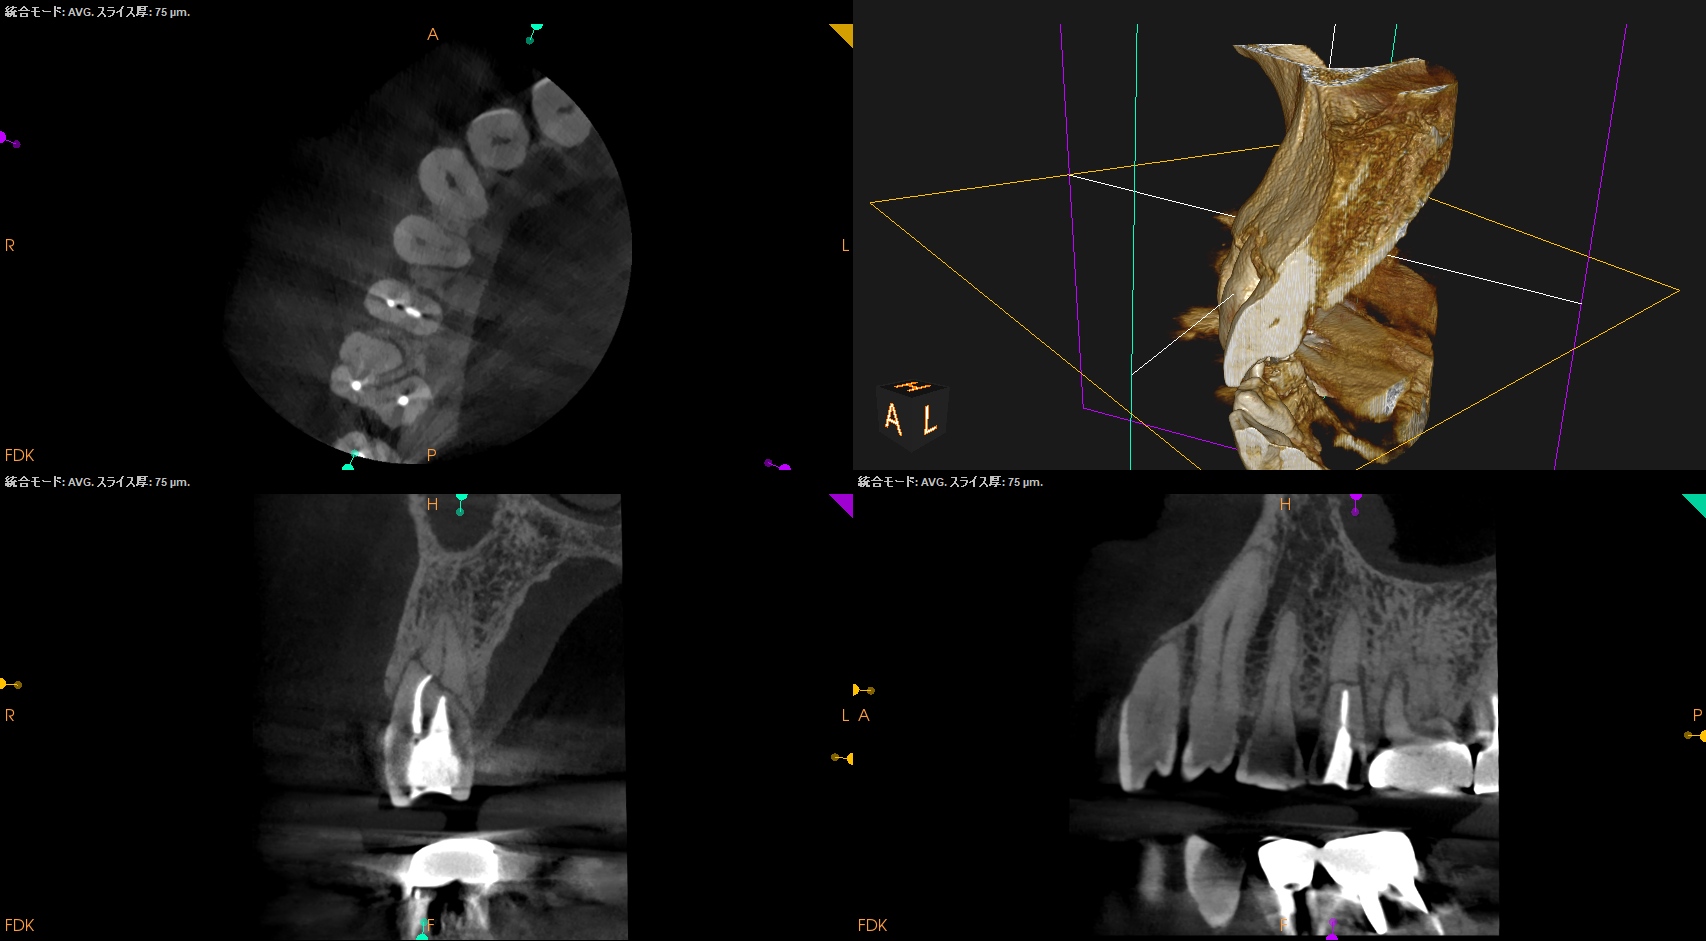

CBCT(2024.10.28)

#4

歯根の中央で水平に破断している。

ここで重要なことは破折片の口蓋側寄りの歯根には病変がないということだ。

ということは…

そこは根管治療が不要である。

治療のゴールとしては、

このような形状に落ち着くのがベストであると言えるだろう。